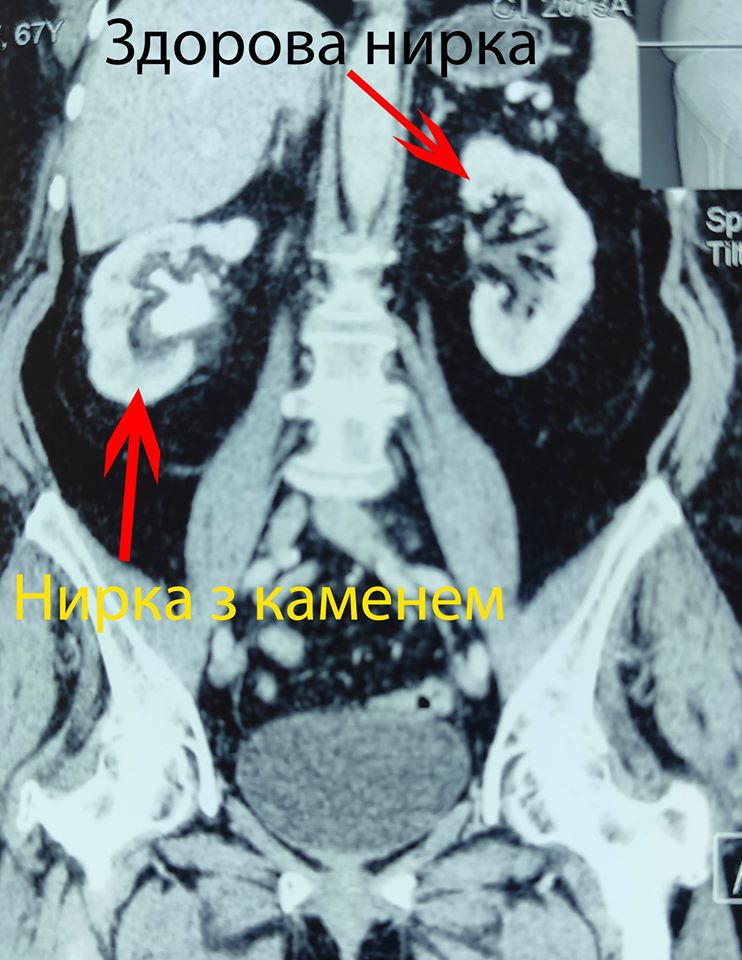

«Відновлення планових оперативних втручань в центрі ендоурології Ковельського МТМО почалося з непростої операції – видалення кораловидного каменя правої нирки через єдиний мініатюрний прокол на шкірі 5 мм.

Камінь займав всю порожнину нирки. Під час операції конкремент поступово вдалося видалити повністю. На даний час пацієнт почувається задовільно і проходить післяопераційну реабілітацію.